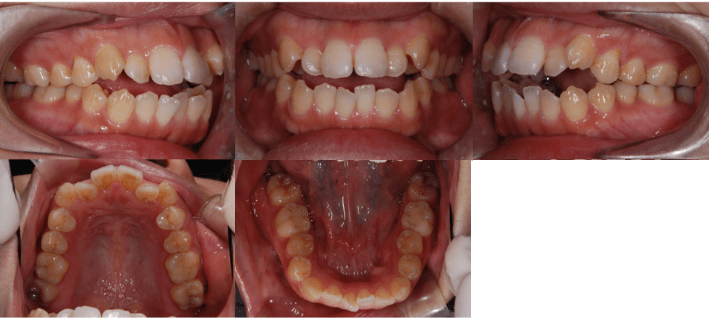

Before

治療前

• 初診時年齢:28歳4ヶ月

• 主訴:前歯のかみ合わせ

• 診断:開咬

• 治療内容:小臼歯4本を抜歯した後に、インビザラインを使用して主訴である開咬の改善を行いました。

• 治療期間:2年

• リスク:矯正治療による歯の移動に伴う痛み、歯根吸収、虫歯

• 費用:80万円